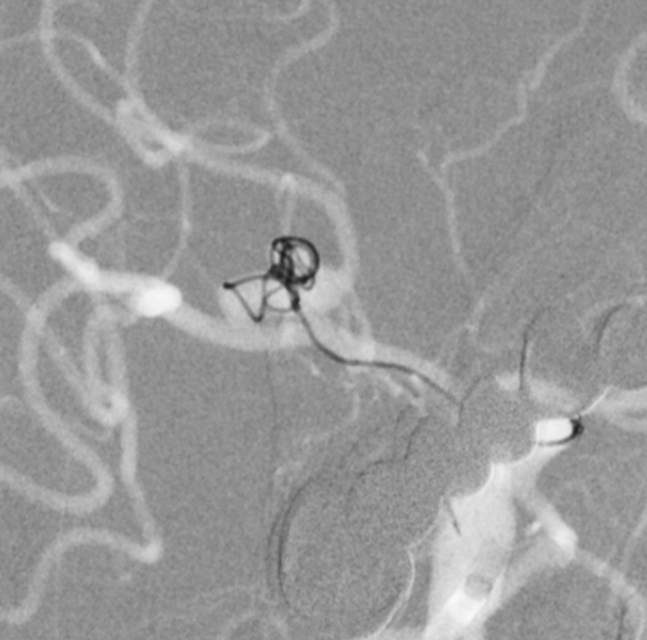

话归正传,下面我们看看如何分兵使用“犄角之势”的策略夹击栓塞“犄角之势”的硬骨头(分叉部绝对宽颈带有俩角的动脉瘤):两个微导管先后到位,两个子囊内的弹簧圈相互依偎,形成“犄角之势”,共同击杀两者之间的大本营(共同的瘤体),最终致密栓塞动脉瘤,消除了动脉瘤再次兴风作浪(再出血)的风险,也最大限度的保全了各个分支血管(粮道)的安全,急性期也没有使用支架,降低了费用,还保障了安全。

栓塞一个复杂动脉瘤,就是进行一场战争。采用“犄角之势”致密单纯栓塞动脉瘤后,指挥者(术者)没有支架内血栓的顾虑,也不担心再出血的侵扰,还有止血药、降压药的保驾护航,可以安心班师回朝了~~~